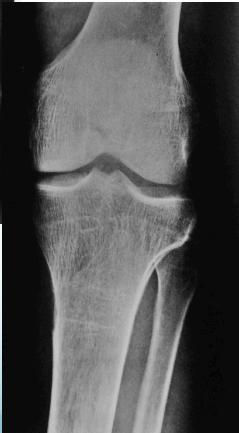

- Sub-periosteal resorption: middle phalanges, tibial shaft

- In hand, sub-periosteal bone resorption .This change usually happen in the middle phalanges, radial aspect in the 2nd or 3rd finger.

- Terminal tuft erosion.

Sub-periosteal bone resorption

- Most useful sign

- Virtually Diagnostic

- Location

Subperiosteal bone resorption (straight arrow), resorption of the tip of the terminal phalanx and the altered bone architecture. Arterial calcification is also present (curved arrow).